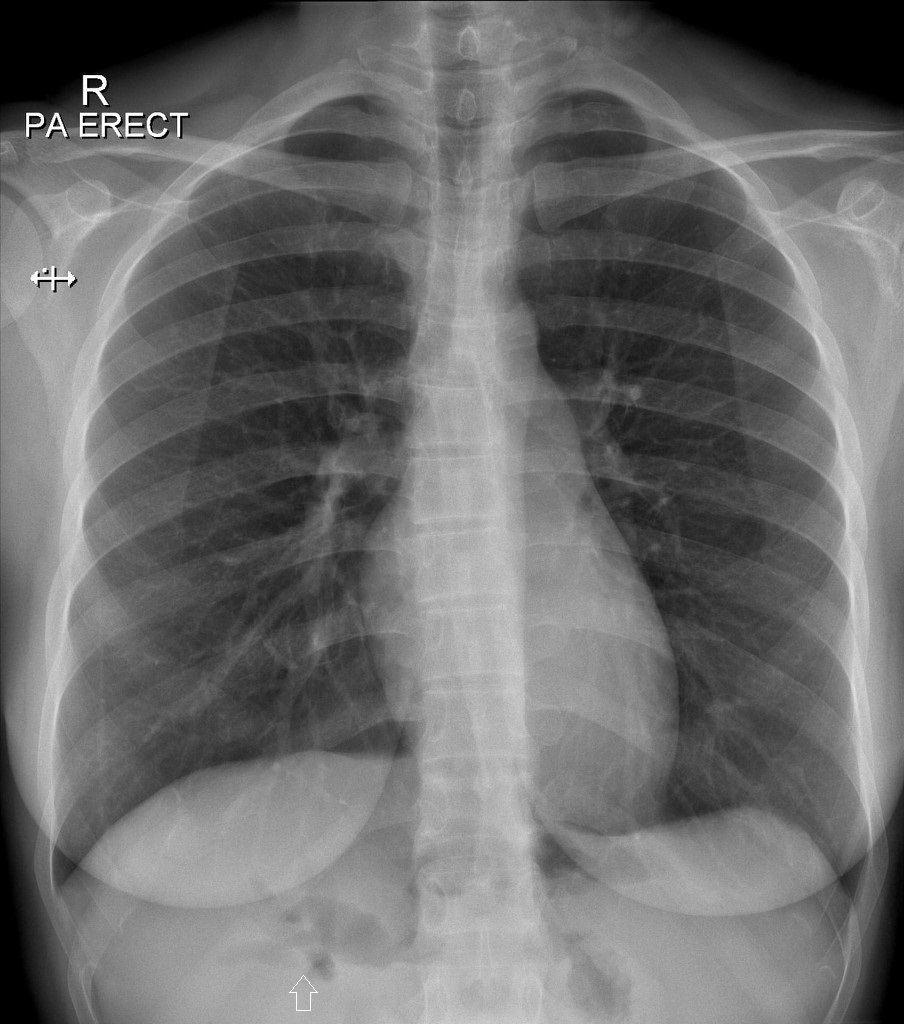

Khí đường mật

Khí đường mật - Ảnh 3

» Thông tin: Nữ giới – 30 tuổi.

» Lâm sàng: Đau mạn sườn phải / Tiền sử cắt túi mật.